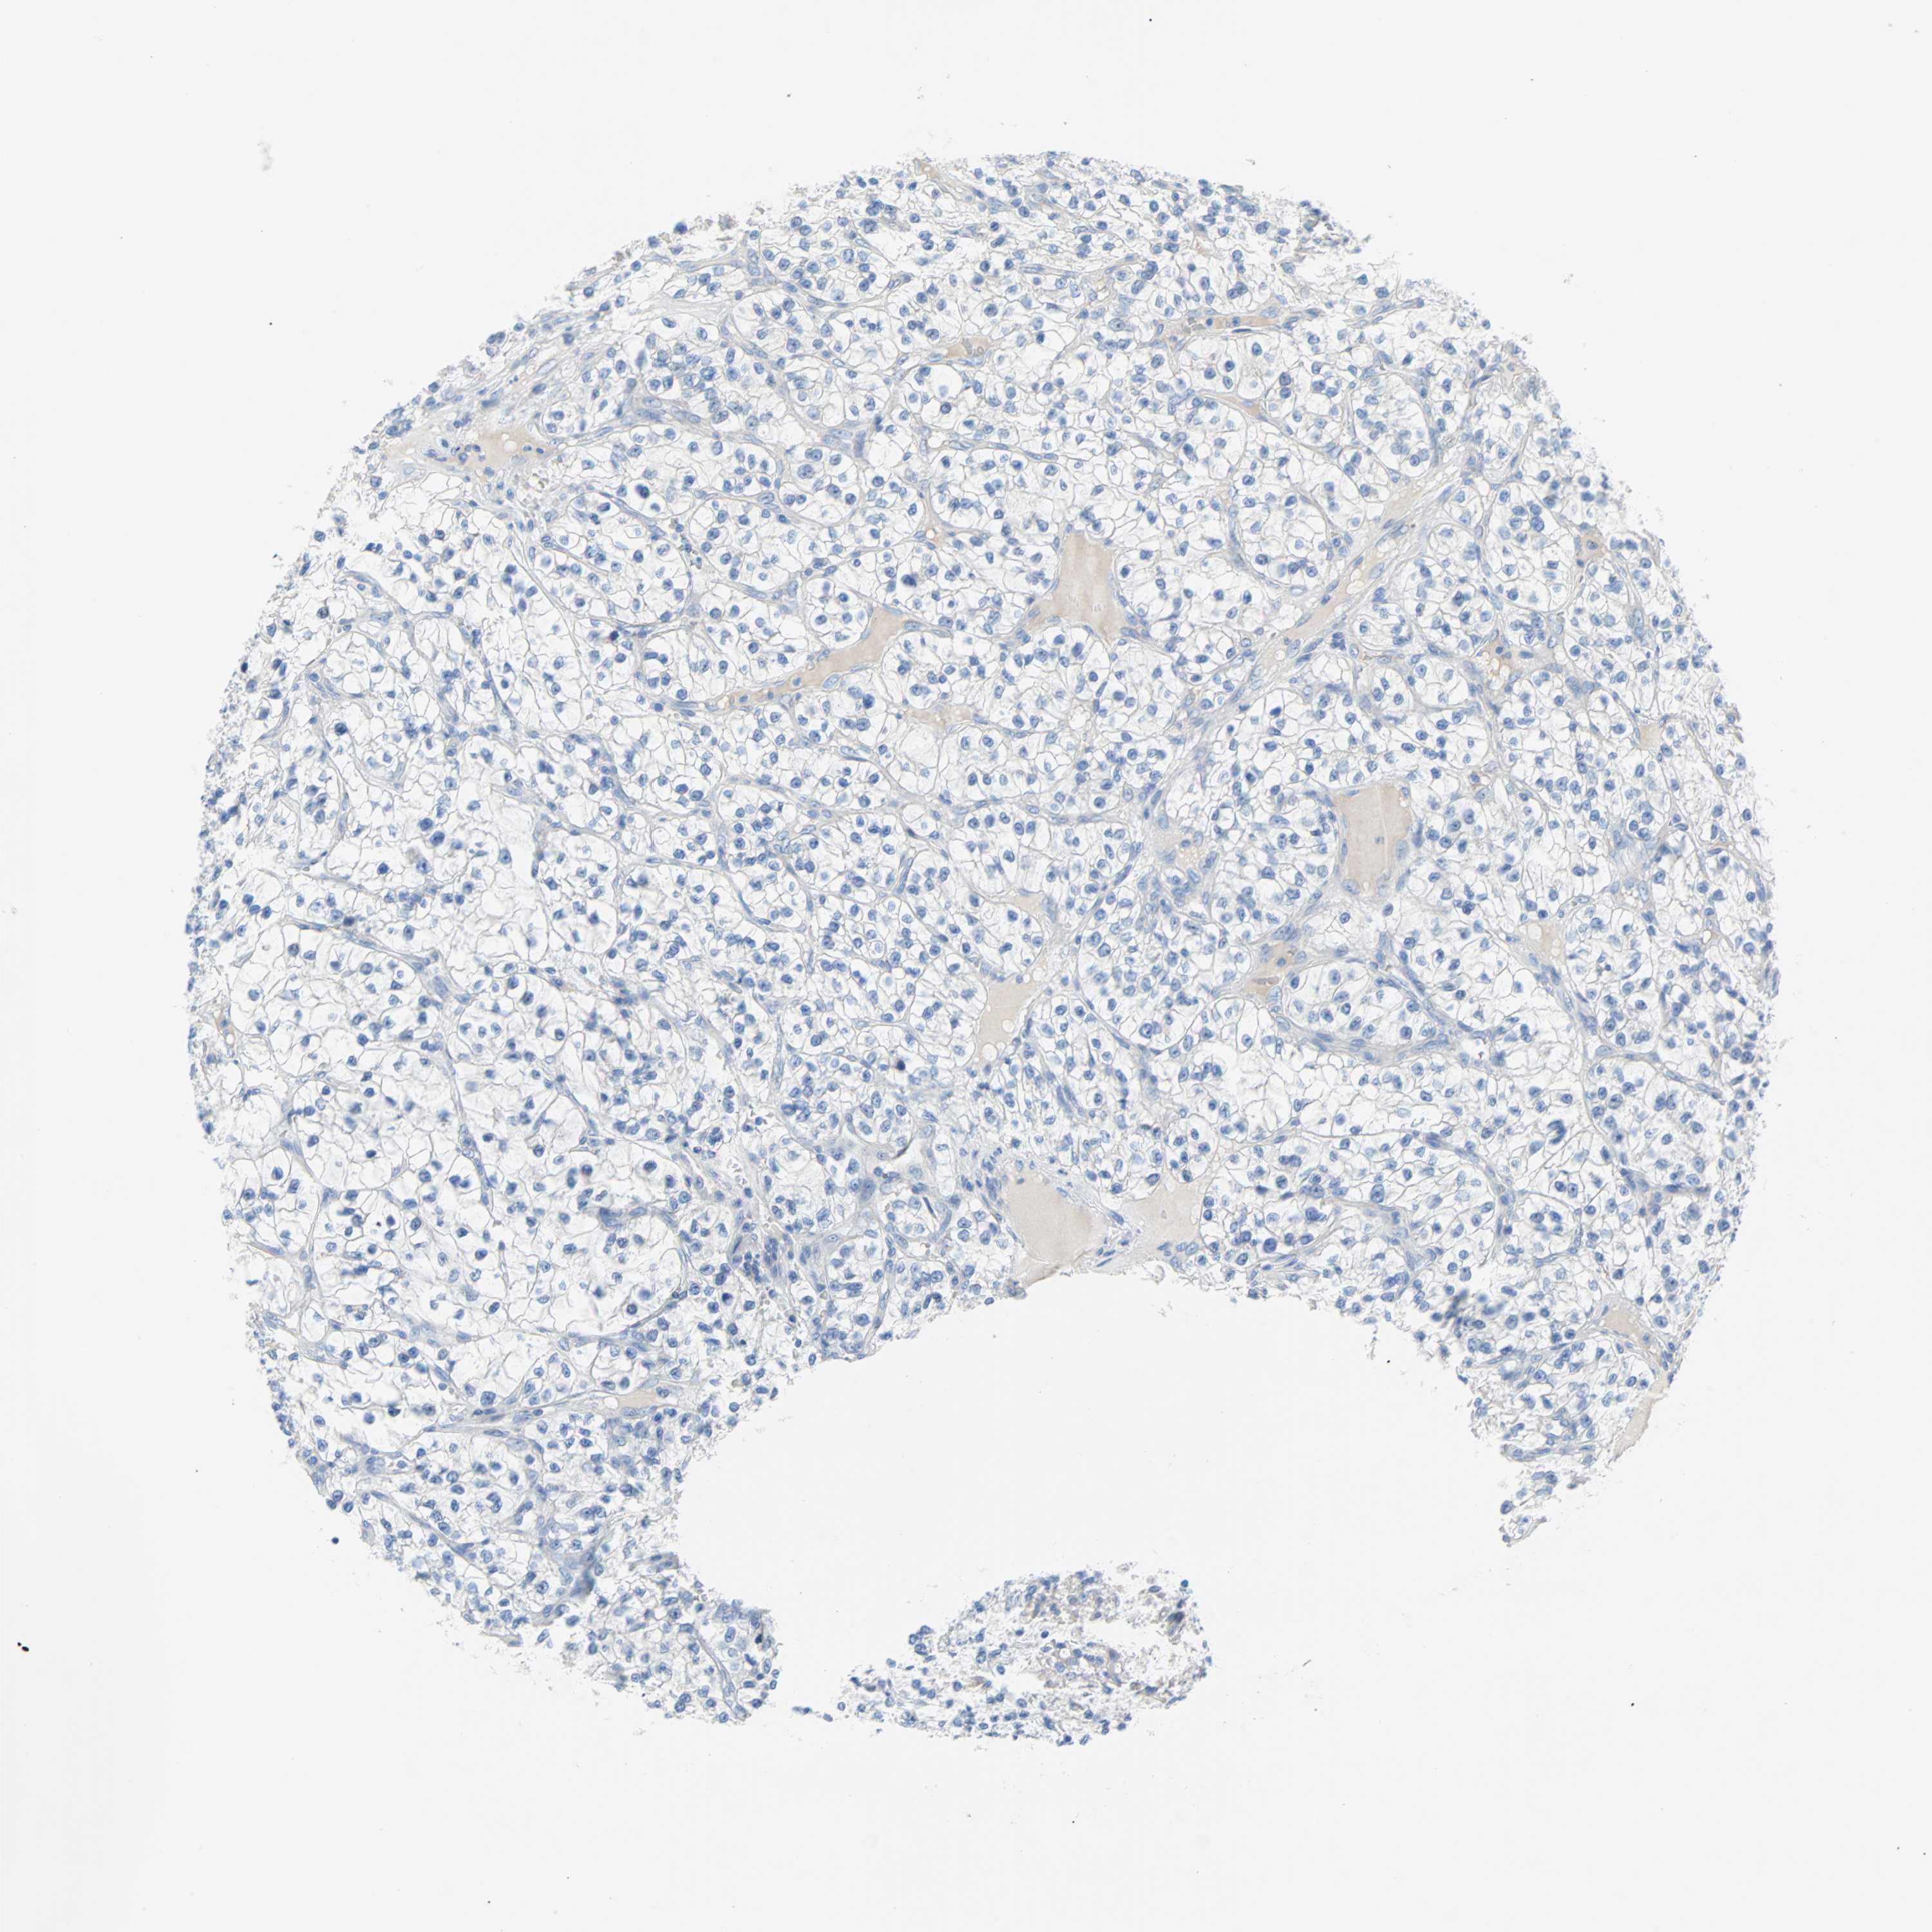

Average pTPM 5.3

Number of samples 64